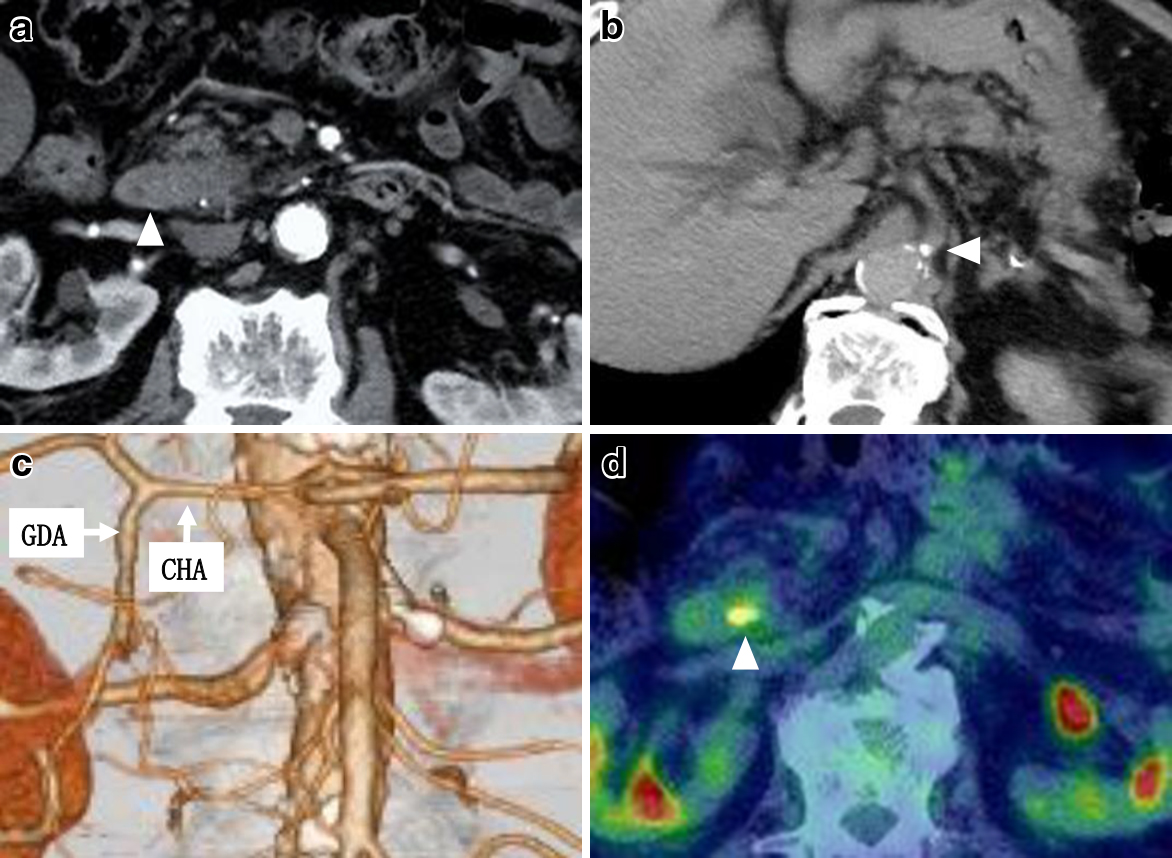

腹部造影CTでは胆管拡張を認め,下部胆管に途絶像を呈していた.下部胆管には22×14 mm程度の遷延性に造影される結節を認めた(Fig. 2a).主膵管の拡張は軽度であった.肝臓や傍大動脈リンパ節への転移を疑う所見は認めなかった.CA起始部の石灰化は認めたが,胃十二指腸動脈(gastroduodenal artery;以下,GDAと略記)・下膵十二指腸動脈(inferior pancreaticoduodenal artery;IPDA)・膵内血管アーケードの著明な拡張は認めなかった(Fig. 2b, c).

Preoperative CT, 3D vascular structure and PET. a: Enhanced abdominal CT showed a 22×14 mm mass near the lower bile duct (arrowhead). b: Abdominal CT demonstrated calcification at the celiac axis (arrowhead). c: CT scan with 3D arterial reconstruction. d: Enhanced abdominal PET showed a 22 mm mass in the lower bile duct (arrowhead).

PET-CTは下部胆管に14×14 mm大の結節とSUVmax:8.1の異常集積を認めた(Fig. 2d).その他に異常集積は認めなかった.